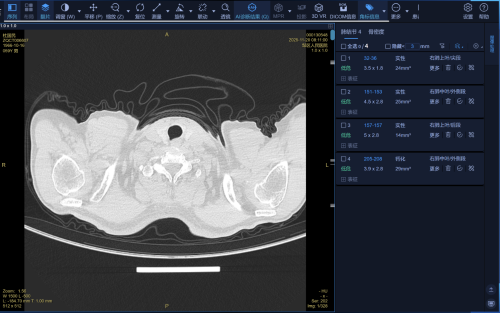

图1 影像AI辅助诊断服务